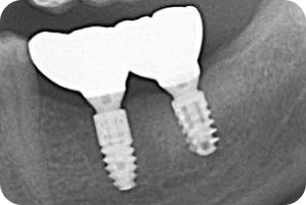

Дентальна імплантація– це найсучасніший, фізиологічний та довготривалий метод відновлення зубів.

Наша стоматологічна кліника вже майже двадцять років пропонує передові рішення з дентальної імплантації зубів. Сучасні світові бренди імплантатів, які мі встановлюємо абсолютно комфортно для вас, повертають повну функціональність та естетику вашим зубам, та вашій посмішці, забезпечуючи довговічній та надійній результат.

✅ Сучасні технології- використовуємо найсучасніші технології та всесвітньовідомі сістеми дентальних імплантатів, які скорочують час реабілітації.